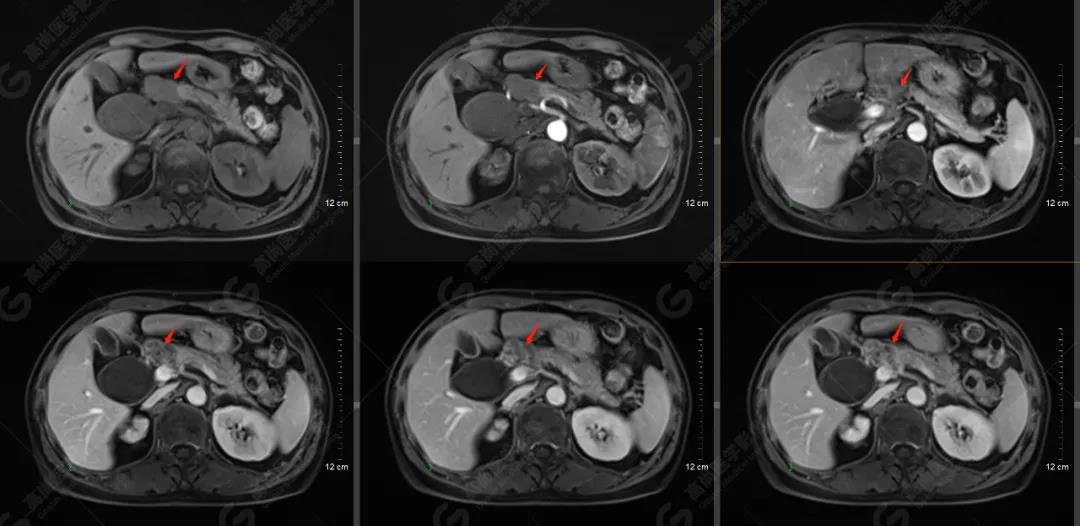

MR檢查所見:胰頭可見結(jié)節(jié)狀異常信號影,大小約2.5×1.8cm,T1WI呈稍低信號,T2WI呈略高信號,信號欠均勻,DWI可見彌散受限,病灶與周圍正常胰腺組織分界欠清,Gd-DTPA增強(qiáng)掃描病灶呈明顯不均勻強(qiáng)化;病灶相應(yīng)節(jié)段上方膽總管明顯囊腫擴(kuò)張,大小約6.4×4.0cm。肝內(nèi)膽管輕度不均勻擴(kuò)張,以左支為著,呈軟藤征。胰管未見擴(kuò)張。胰頭上緣及腹膜后(腹主動脈旁)見腫大淋巴結(jié),增強(qiáng)掃描可見中度強(qiáng)化,部分強(qiáng)化不均勻;腹腔未見積液。

提示: 胰頭占位性病變,性質(zhì)考慮為胰腺癌并胰頭上緣、腹膜后多發(fā)淋巴結(jié)轉(zhuǎn)移

肝內(nèi)膽管輕度擴(kuò)張,膽總管囊狀擴(kuò)張